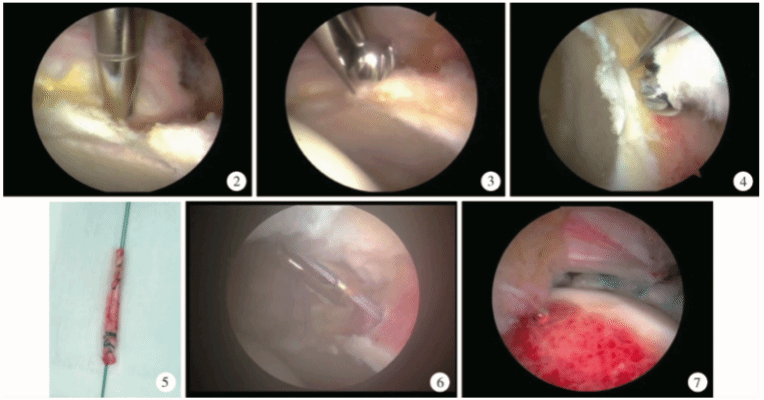

髋组进一步开展髋关节镜下盂唇重建手术,相关手术技术更加更熟完善,取得了良好的临床效果,并创新性的提出了微创膝关节外侧小切口取自体髂胫束的新型取腱方式,进一步提高取移植物的速度,减小取腱创伤,改进手术流程。